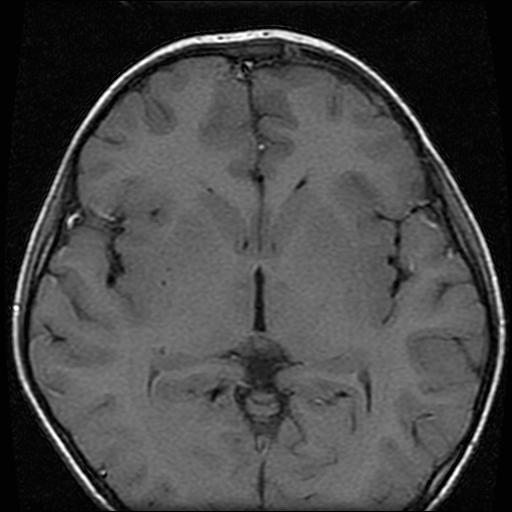

6岁小儿,左侧视神经瘤术后。现左侧视力减退。